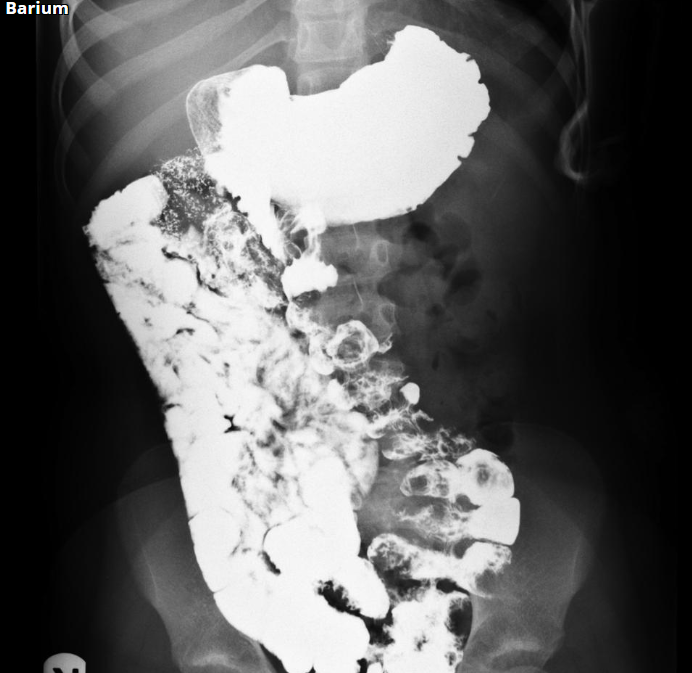

Homem, 45 anos, Dor abdominal, distensão e parada da eliminação de fezes e flatos.

Hérnia interna - pericecal.

Causa de obstrução intestinal de delgado.

Segundo tipo mais comum de hérnia interna, perdendo para a paraduodenal.

A alça herniada geralmente consiste em um segmento ileal que se projeta através de um defeito no mesentério cecal (que pode ser congênito ou adquirido)